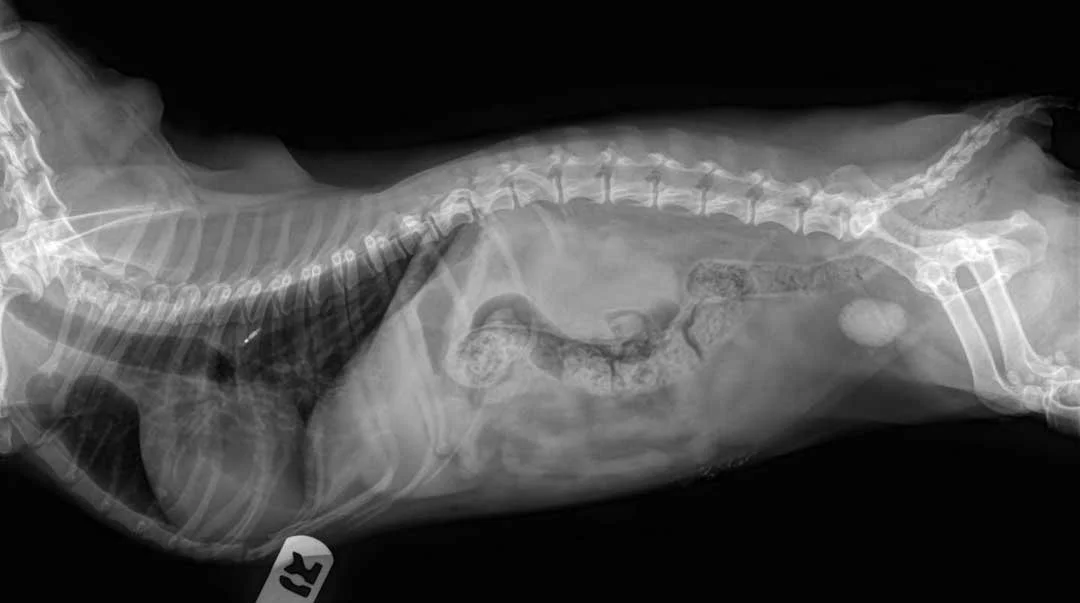

We use advanced diagnostic tools like ultrasound and digital X-rays to better understand what’s happening with your pet’s health. Our team also offers a variety of in-house and send-out lab services for blood work and other testing, ensuring your pet gets the care they need quickly and accurately

X-ray image of a dog lying on its side showing internal organs, spinal column, and bones.